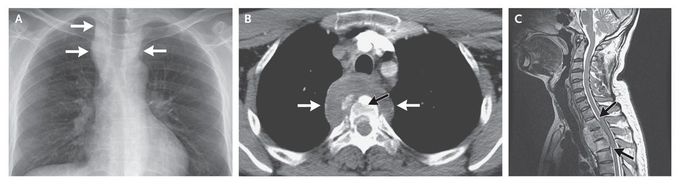

A 20-year-old man who was originally from Bangladesh presented to our clinic with a 6-month history of anorexia and weight loss. The physical examination was remarkable for a temperature of 39°C. Chest radiography showed a mass that appeared to be located in the posterior mediastinum (Panel A, white arrows). Computed tomography (CT) of the chest showed a paravertebral mass of soft tissue surrounding the vertebra (Panel B, white arrows), with destruction of vertebral bodies (black arrow). The mass extended from T1 to T5. Magnetic resonance imaging revealed compression and posterior displacement of the spinal cord without infiltration from the mass (Panel C, arrows). A specimen of the mass was obtained with CT-guided aspiration. The results of Ziehl–Neelsen staining of the tissue were positive, and Mycobacterium tuberculosis grew in a culture of the tissue, indicating Pott's disease. Antituberculous chemotherapy was prescribed. Subsequent radiographic studies showed that the mass had regressed, and the patient's clinical symptoms resolved within 3 months.